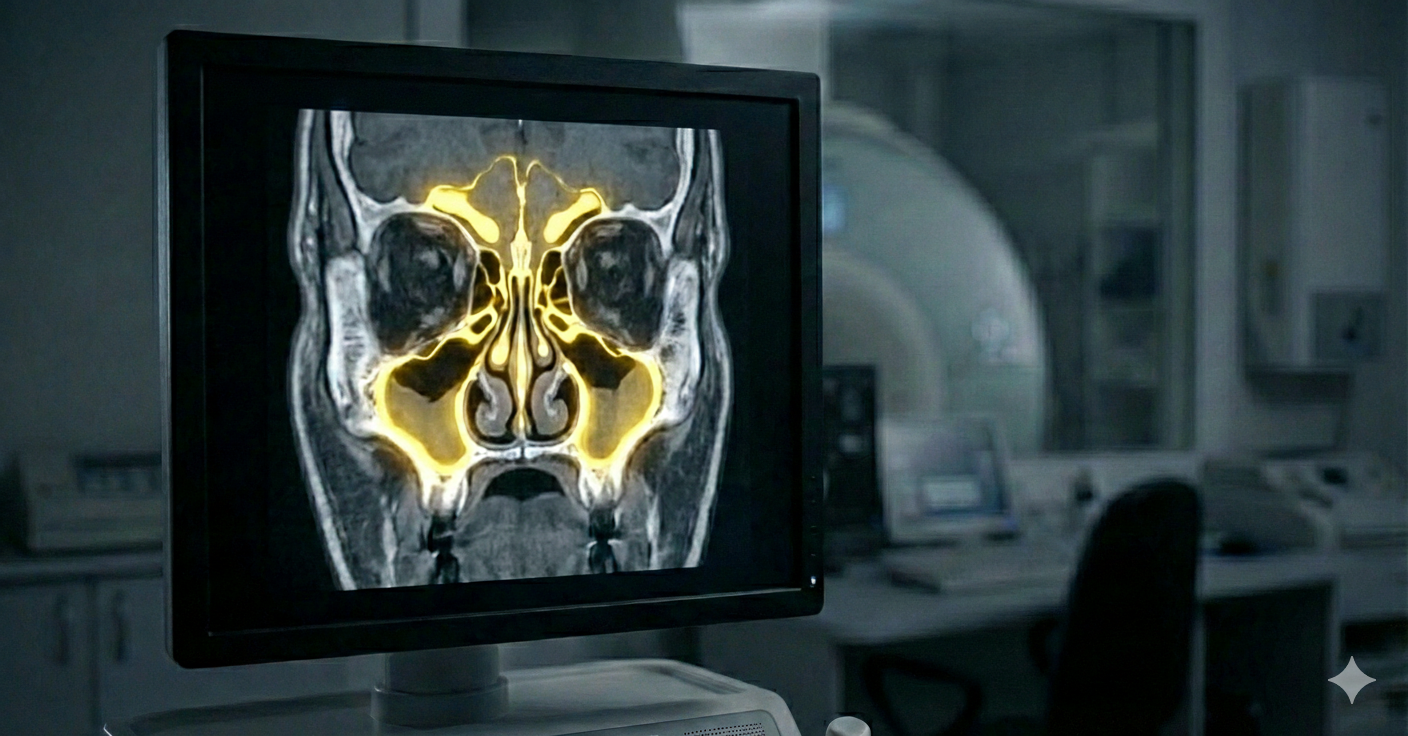

Це найбільш інформативний метод дослідження шиї, який створює детальні 3D-зрізи хребців, міжхребцевих дисків та спинного мозку. На відміну від рентгену, МРТ «бачить» не лише кістки, а й м’які тканини. Це дозволяє нам точно діагностувати:

Чому важливо робити МРТ шиї з контрастом? Контрастна речовина «підсвічує» активні вогнища хвороби. Це дозволяє лікарю зрозуміти: хвороба зараз у стані загострення чи в ремісії. Потужність нашого апарату 1.5 Тесла критично важлива для пошуку найдрібніших осередків, які можуть «пропустити» слабші сканери. МРТ-апарат Philips Achieva створює надчіткі 3D-зображення внутрішніх органів та систем у рекордно короткі терміни. Це означає, що ви проводите в апараті менше часу, отримуючи при цьому максимально деталізований результат.